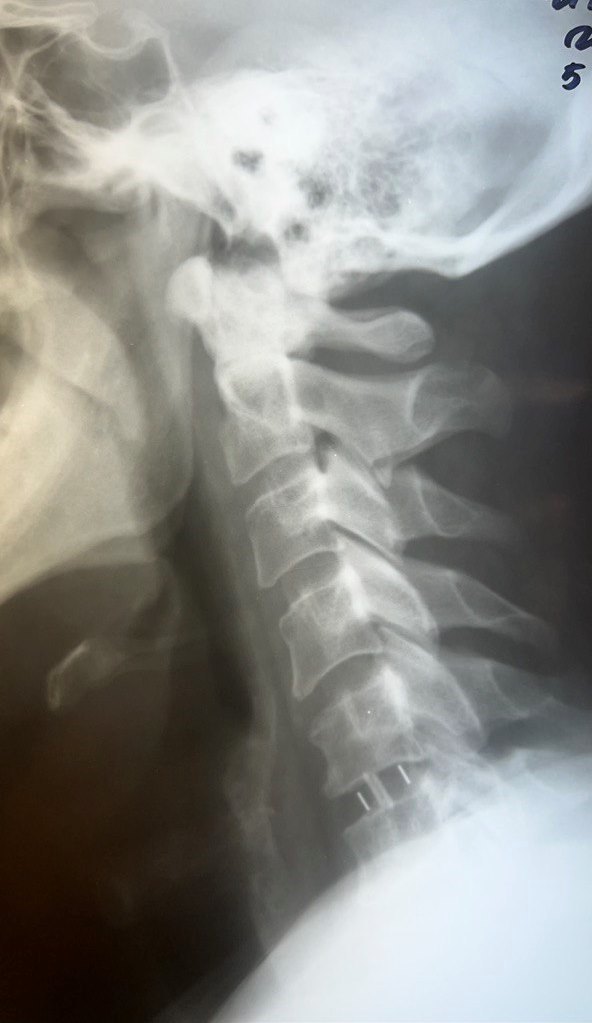

Врачи провели необходимые обследования и установили диагноз: грыжа диска С5-С6, спондилоартроз (дегенеративное поражение межпозвонковых суставов, которое затрагивает хрящи, костные ткани, связки и околосуставные мышцы), корешковый синдром (радикулит) С6 справа с чувствительными и двигательными нарушениями.

Нейрохирурги Владимир Дронов и Евгений Дронов осуществили микрохирургический передний доступ на шее. Специалисты удалили межпозвонковый диск и грыжу C5-C6 с использованием операционного оптического прибора, микрохирургической техники и инструментария. Помимо этого, была устранена компрессия спинного мозга и нервных корешков, а также установлен межтеловой кейдж — металлическая конструкция, которая размещается между двумя соседними позвонками и соединяет их между собой.